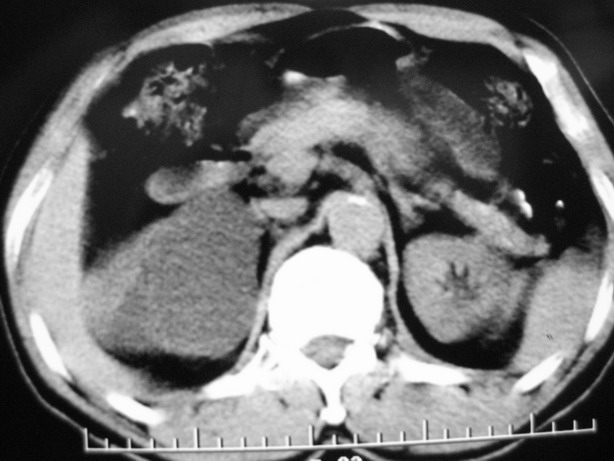

标题: CT10772:男性,48,右肾盂旁多囊性占位! [打印本页]

男性,48,体检发现,平时无症状。

收集期:

延迟期造影剂没有进入囊性病灶内考虑多发性肾囊肿,包括一个盂旁囊肿。

肾盂旁多囊性占位,有实性成分,增强有轻度强化,收集期病变内无造影剂显影。诊断肾盂旁囊肿,有实性成分无法解释,查书后诊断为:多房性囊性肾瘤!!不知大家同意否?????????对本病知道不多,望大家不吝赐教!!

右肾多发囊性低密度影,囊内有增强的隔及实性组织,考虑囊性肾癌。